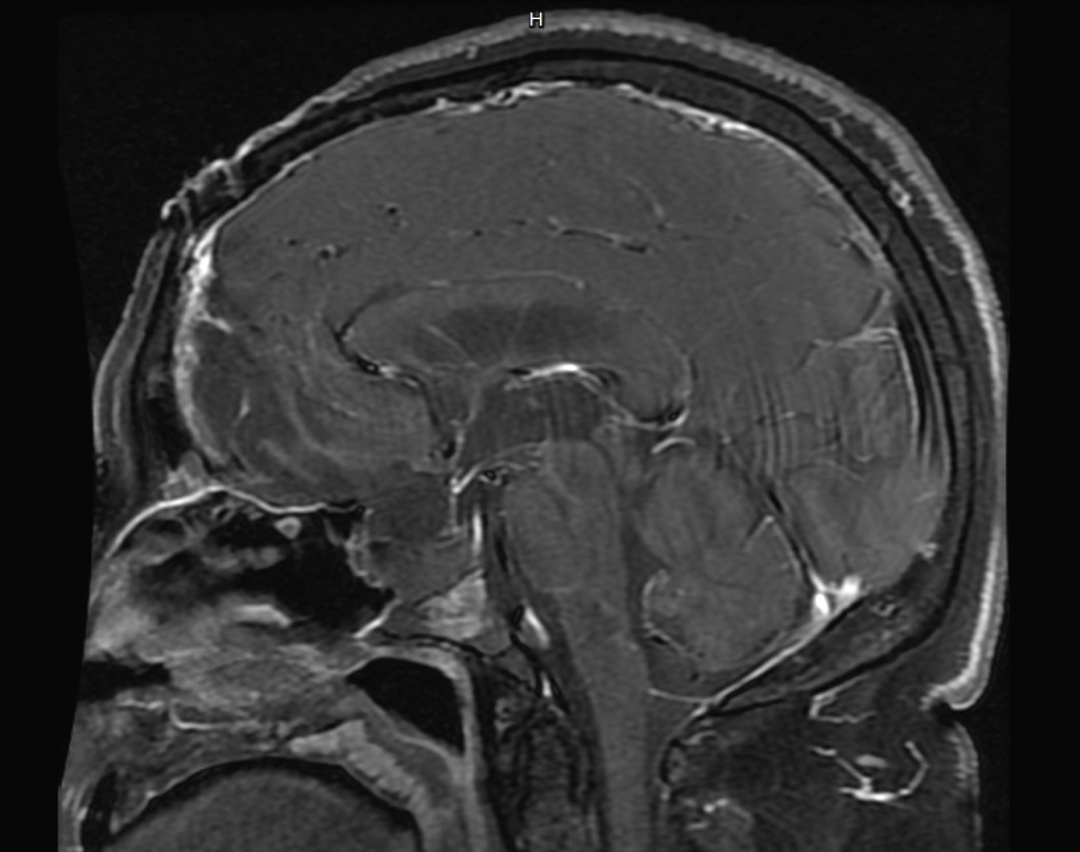

手术后